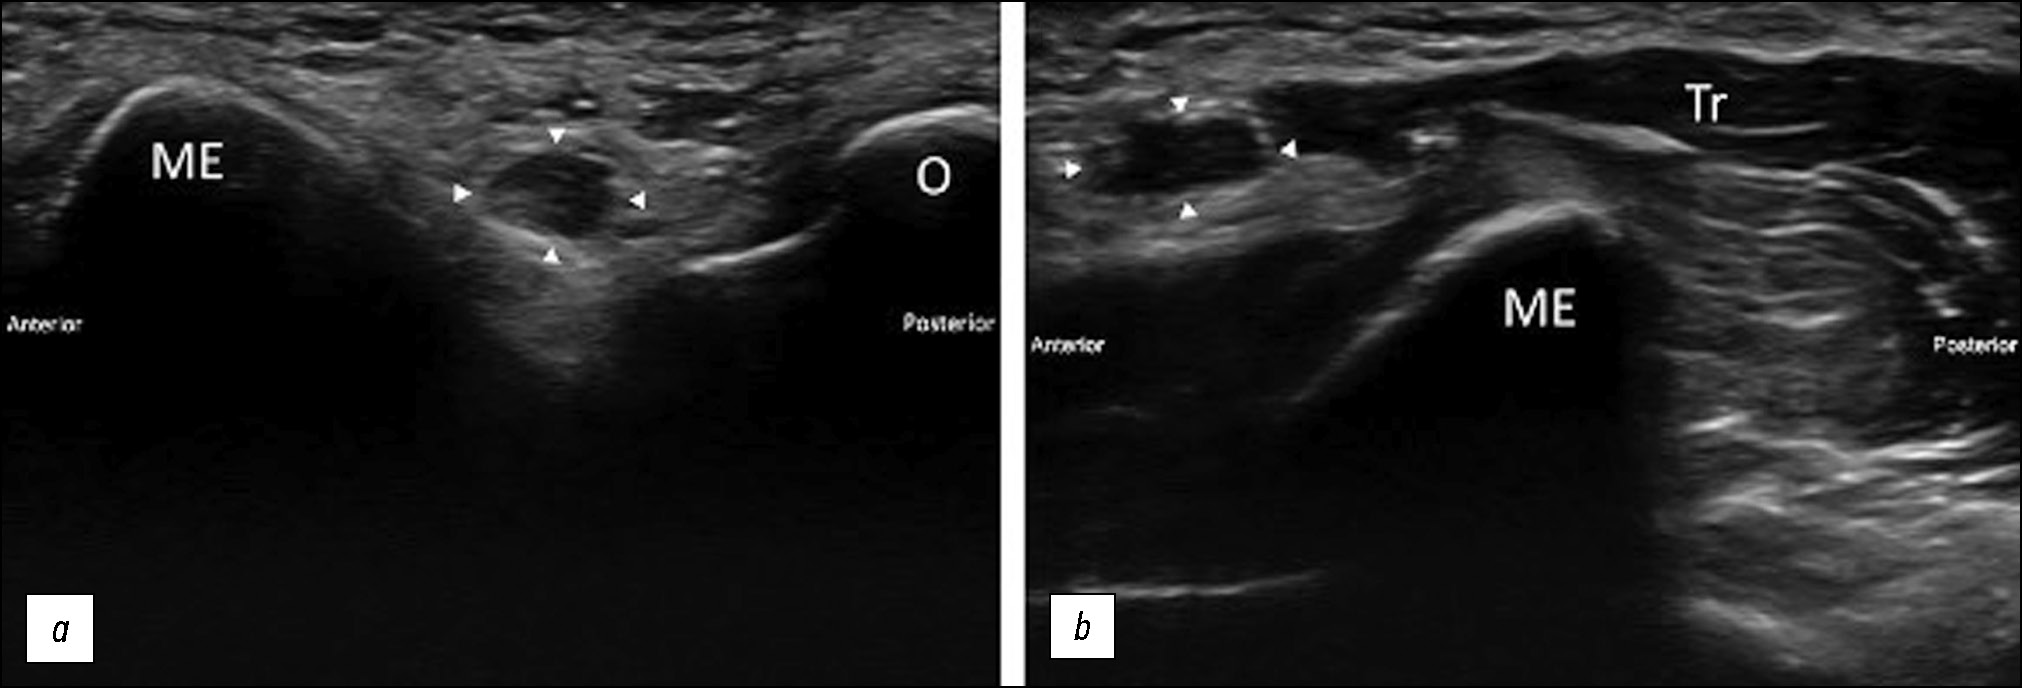

Единственным достоверным методом диагностики является УЗ-диагностика в динамическом режиме, о чём свидетельствует исследование H.J. Chuang и соавт. от июля 2016 года [10], где визуализировано, как локтевой нерв и медиальный край дистальной части трёхглавой мышцы были подвывихнуты во время сгибания локтя более чем на 100 градусов и вернулись в анатомическое положение во время разгибания в локтевом суставе (рис. 5). МРТ и рентгенография обычно не приносят результата.

Рис. 5. Ультразвуковое изображение медиальной части локтевого сустава: a — при разгибании в локтевом суставе локтевой нерв (указанный стрелкой) располагается между медиальным надмыщелком плечевой кости (МЕ) и локтевым отростком локтевой кости (О), локтевой нерв выглядит отёчным и гипоэхогенным; b — во время сгибания в локтевом суставе локтевой нерв (указанный стрелкой) и медиальная часть трёхглавой мышцы (Tr) скользят вперёд по медиальному надмыщелку (ME) [10].

Fig. 5. Ultrasonographic imaging of the medial elbow (short-axis view): a — in elbow extension, the ulnar nerve (arrowhead) is located between the medial epicondyle of humerus (ME) and the olecranon of ulna (O), the ulnar nerve apppears as swollen and hypoechoic; b — during elbow flexion, the ulnar nerve (arrowhead) and medial portion of the triceps muscle (Tr) slide anteriorly over the medial epicondyle (ME) [10].